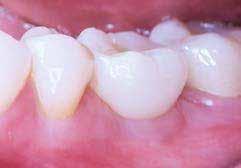

A kész korona átadásakor a páciens elégedett volt az esztétikával, az azóta eltelt évben rendszeres kontrollokon jelent meg, melyek során meggyőződtünk a kemény- és lágyszövetek stabilitásáról (18. és 19. képek).

17. a–b képek: A kész munka átadáskor. 18. a–c képek: 1 éves kontroll. 19. kép: Intraorális kontroll röntgen felvétele 1 évvel az átadás után.